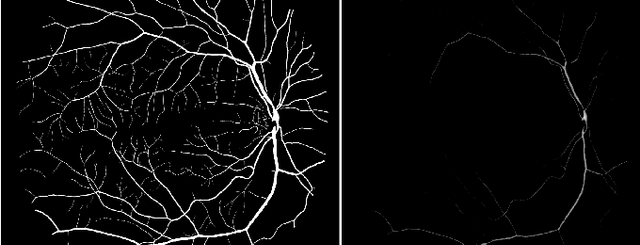

In this work, we have presented a novel method for detection of retinal image features, the optic disc and the fovea, from colour fundus photographs of dilated eyes for Computer-aided Diagnosis(CAD) system. A saliency map based method was used to detect the optic disc followed by an unsupervised probabilistic Latent Semantic Analysis for detection validation. The validation concept is based on distinct vessels structures in the optic disc. By using the clinical information of standard location of the fovea with respect to the optic disc, the macula region is estimated. Accuracy of 100\% detection is achieved for the optic disc and the macula on MESSIDOR and DIARETDB1 and 98.8\% detection accuracy on STARE dataset.